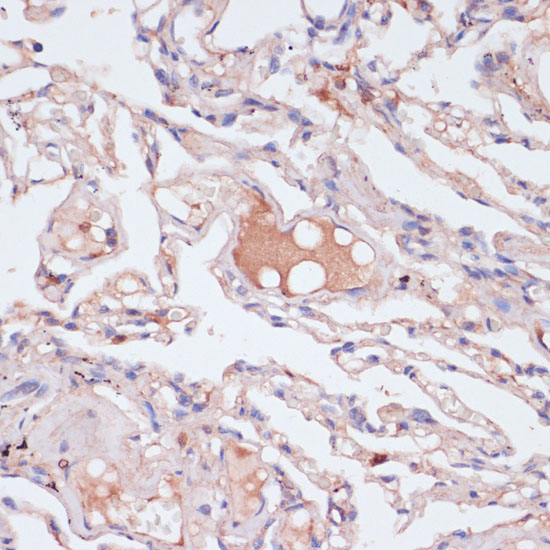

ApplicationWB, IHC; Recommended dilution: WB 1:500 - 1:2000, IHC 1:50 - 1:200